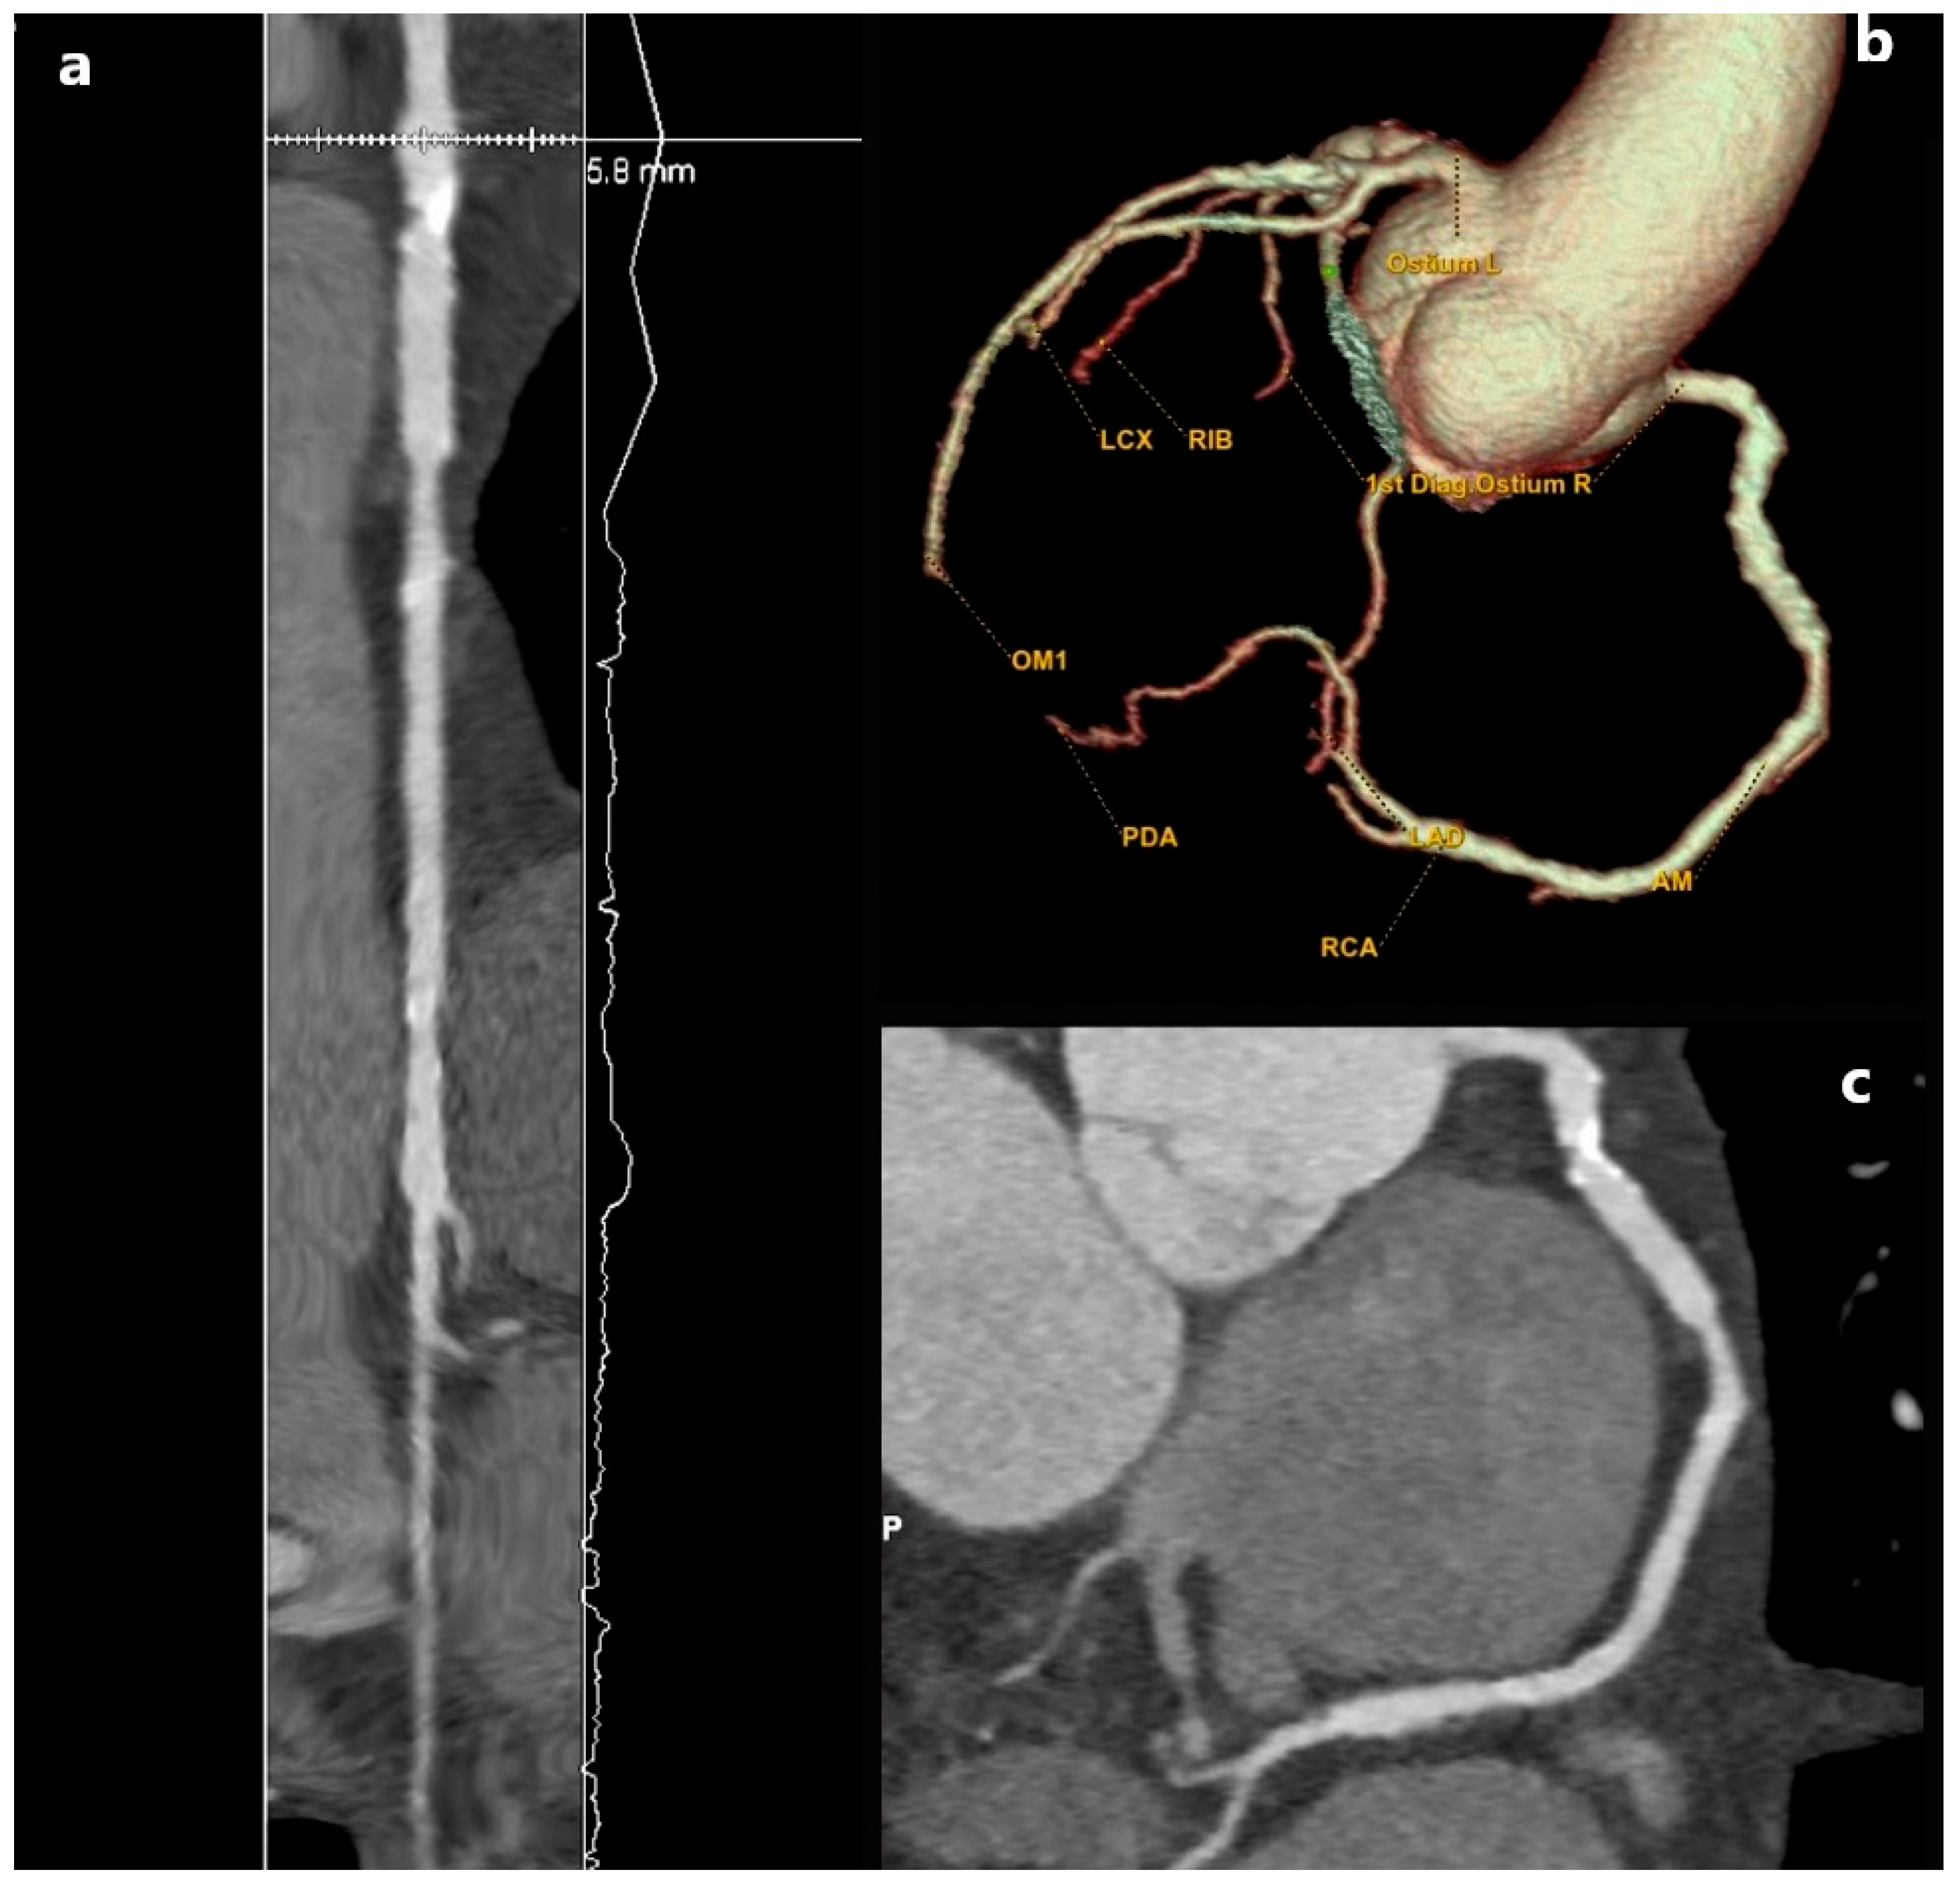

3.1. Myocardial Bridge